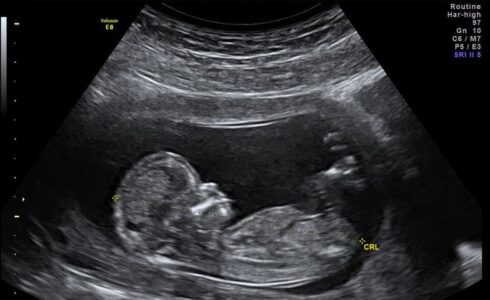

Ask any PRC: an ultrasound drastically increases the possibility that a mother chooses life for her child, and continues seeking resources to help her during an important time. WomanKind shares a few stories of choosing life from their ultrasound room!